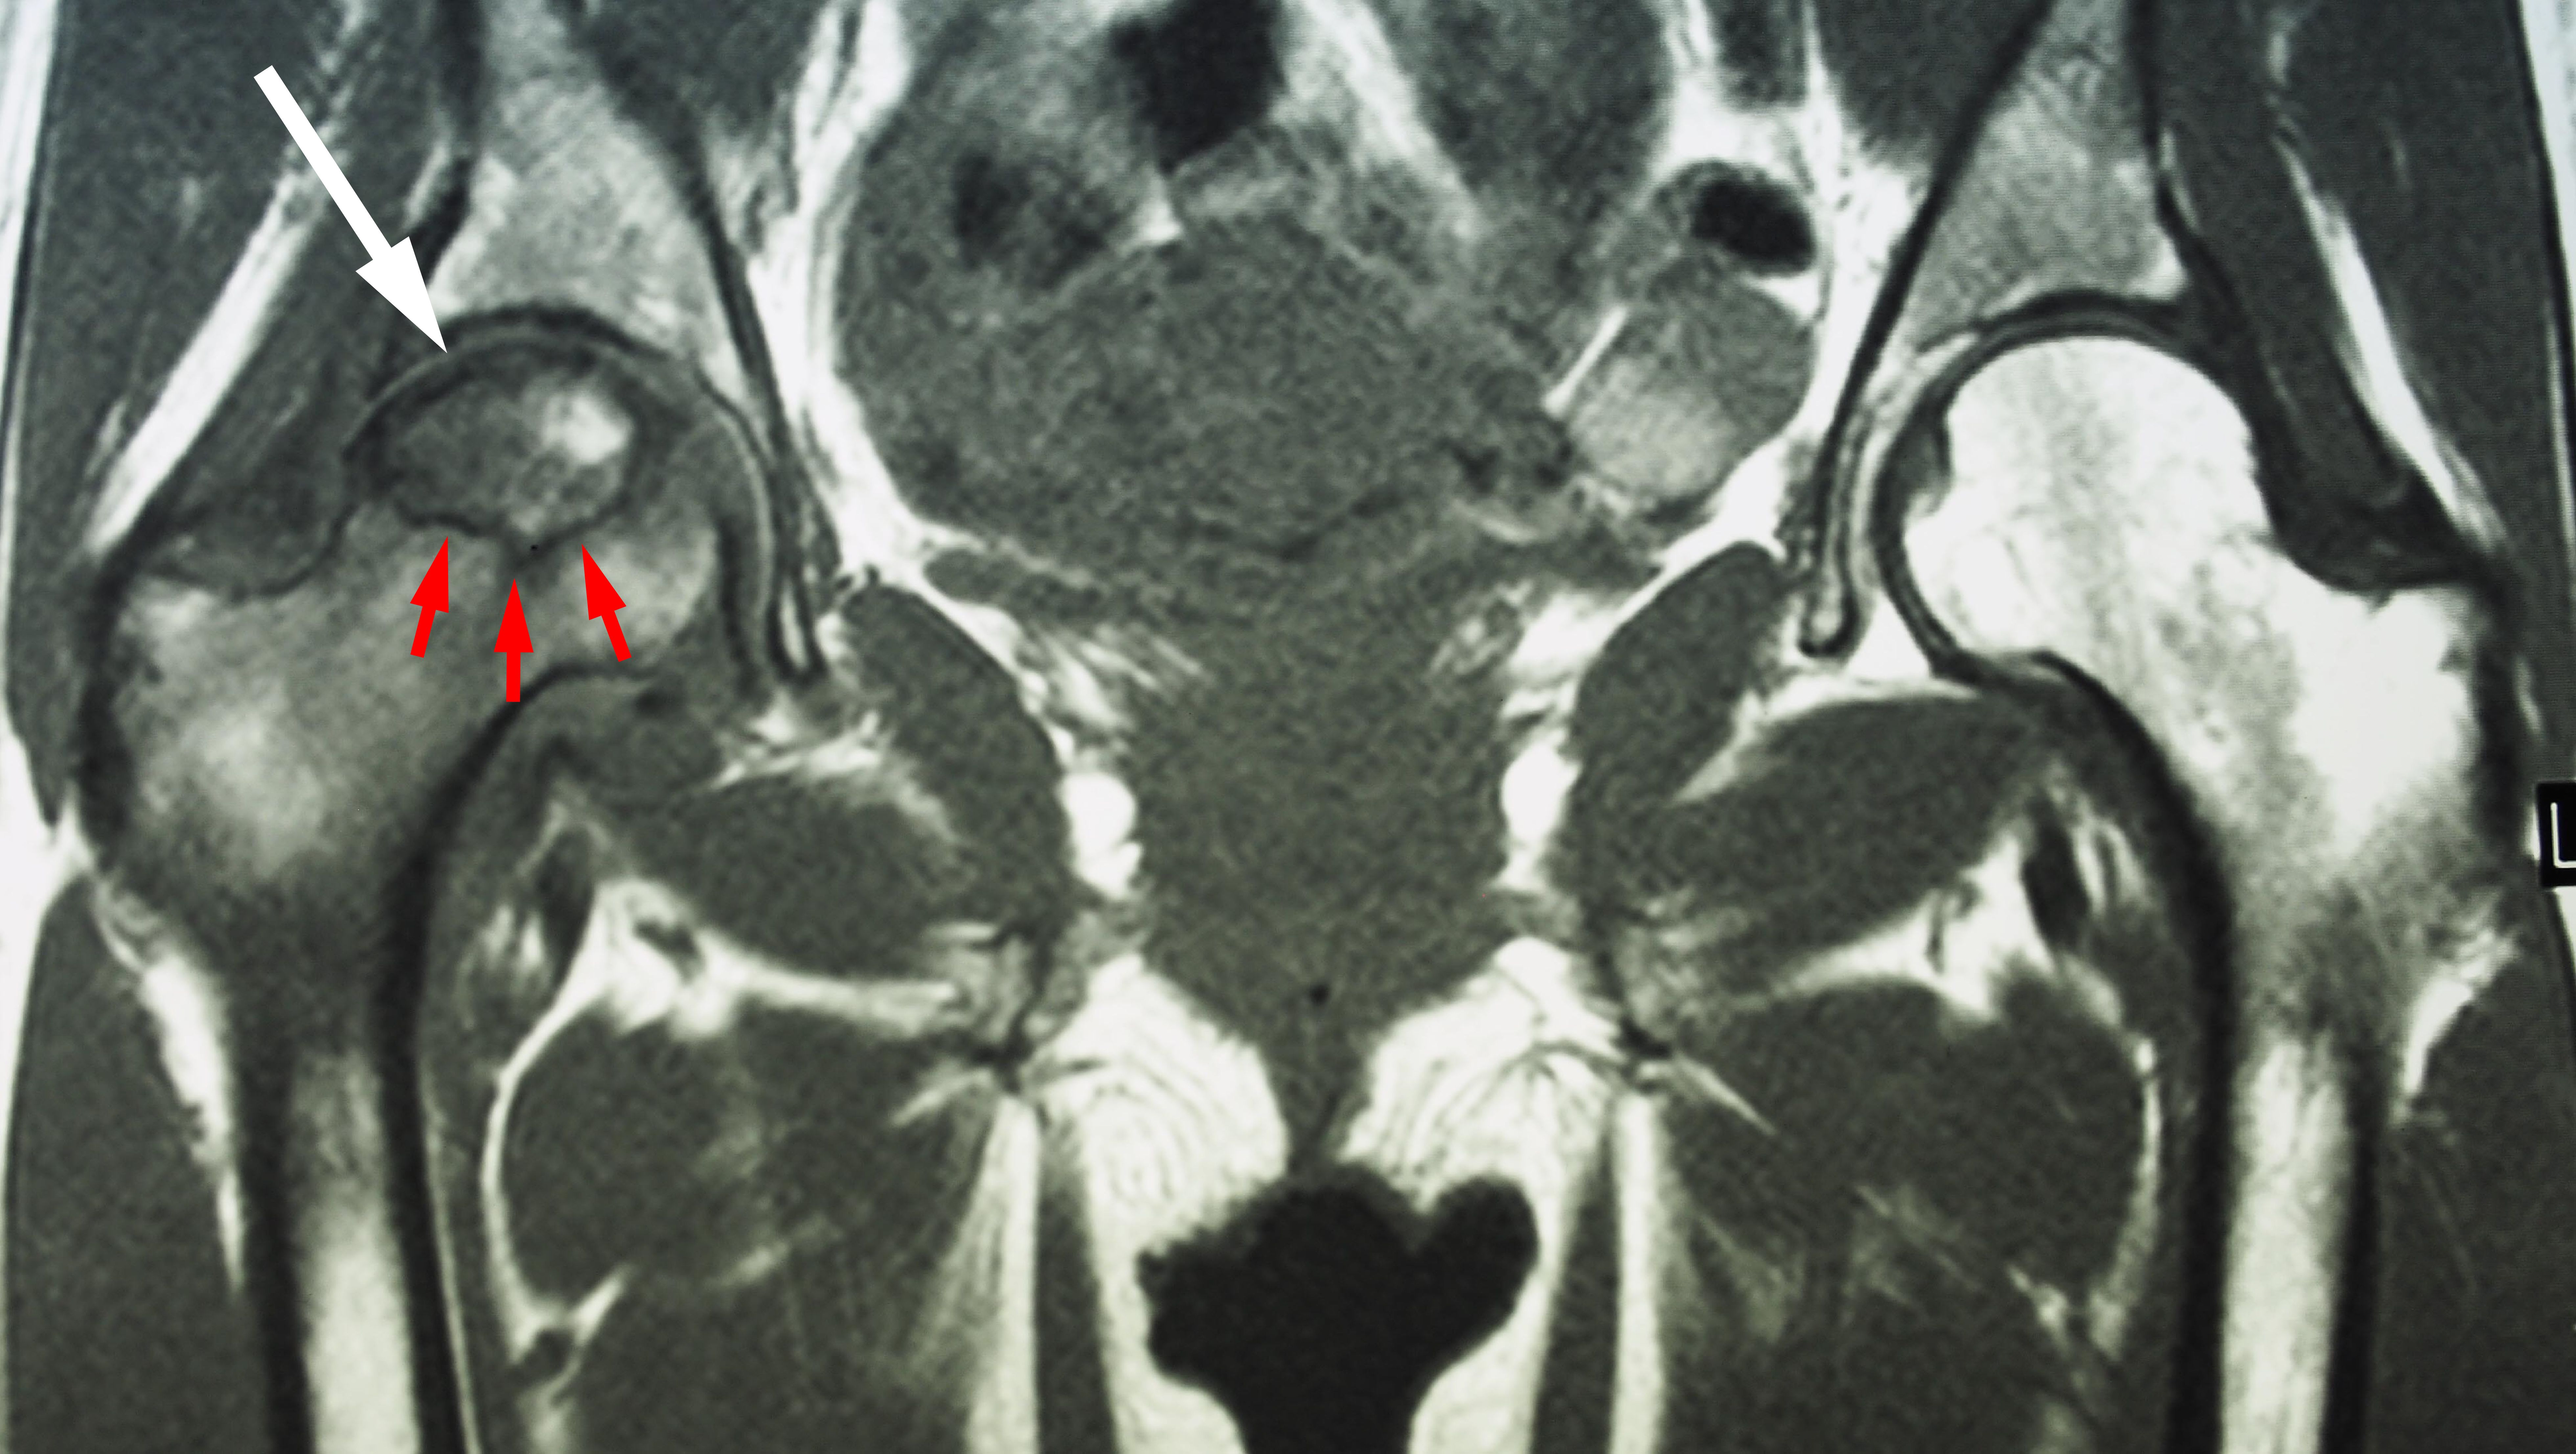

Magnetic resonance imaging (MRI) scans. Early changes in the bone that may not show up on an x-ray can be detected with an MRI scan. These scans are used to evaluate how much of the bone is affected by the disease. An MRI may also show early osteonecrosis that has yet to cause symptoms (for example — osteonecrosis that may be developing in the opposite hip joint).

MRI of osteonecrosis

This MRI scan shows osteonecrosis in a patient's right hip (white arrow). The dark line (red arrows) denotes the border between dead bone and living bone. The patient's left hip is normal.

Image courtesy of Stuart J. Fischer, MD, FAAOS